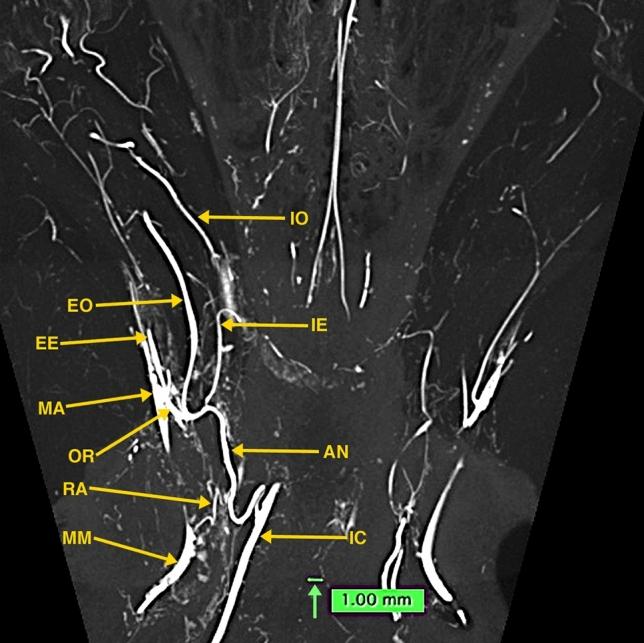

The cavernous carotid inferolateral trunk and persistent primitive maxillary arteries: analysis of dissected arterially injected fetal specimens and high-resolution micro-CT of the dog's anastomotic arteries.

Photographs of fetal specimen dissections demonstrate the cavernous carotid inferolateral trunk. A separate persistent primitive maxillary artery was not present in the dissected specimens. High-resolution micro-CT images of the dog demonstrate homologous arteries with segments of the human inferolateral trunk, and other skull base and brain arteries.

This investigation provides the only photographs in the literature of dissected human fetal cavernous carotid inferolateral trunks. A persistent primitive maxillary artery was not present in the dissected specimens and is a non-existent structure, likely a previously misidentified carotid inferolateral trunk. High-resolution micro-CT images of the dog visualized arteries that are homologous to segments of the human cavernous carotid inferolateral trunk artery.